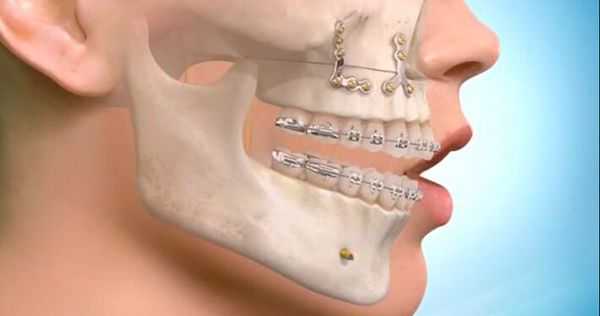

Самым частым методом ортопедического лечения переломов является двучелюстное шинирование — наложение на зубные ряды шин-скоб с репозицией отломков и фиксацией прикуса в привычном для больного положении. Этот метод консервативен и малотравматичен, но в ряде случаев не позволяет получить хорошей фиксации фрагментов верхней челюсти, особенно при высоких и сложных переломах. В среднем при переломах верхней челюсти требуется обездвиживание и ограничение жевательной нагрузки на срок 4-5 недель.

Самым современным и адекватным методом лечения на данный момент является остеосинтез (фиксация титановыми накостными конструкциями) переломов верхней челюсти. Это хирургическое вмешательство, выполняемое из внутриротовых разрезов. При таком варианте лечения можно точно сопоставить и зафиксировать фрагменты для создания условий их сращения [7] .